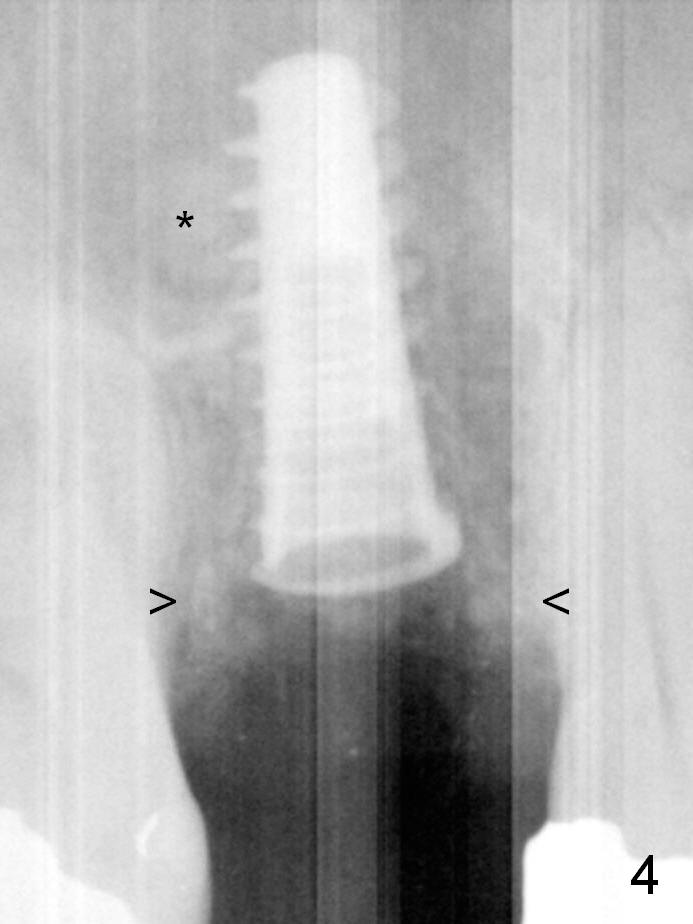

To prevent sinus lift related sinusitis, a shorter implant is going to be placed (Fig.1), approxi-mately 2 mm beyond the apex. Following extraction, the buccal plate (Fig.3a (coronal section): B) is not only ~ 2 mm shorter than the palatal one (P), but also thinner. Since the bone density of the palatal plate is higher, without osteotomy an implant is less likely placed in the middle of the socket (S (Fig.1); Fig.3b) than buccal (Fig.3c). Therefore drills are used to form osteotomy in the apical 1/3 of the palatal slope (Fig.3d (red arrow); SM: sinus membrane). When 3.3 mm Magic Drill (MD) is in place (Fig.2), the distal surface of the sinus septum is perforated without air leakage. Demineralized allograft (.0125-.085) is placed for sinus lift (Fig.4 *) prior to placement of 4.5x11 mm implant with ~ 30 Ncm. The implant is slightly buccal to the ideal position indicated in Fig.3e (curved blue line: sinus lift). A 4.5x4(2) mm pair abutment is placed for an immediate provisional to hold mineralized allograft in the remaining socket gaps (Fig.4 arrowheads, .5-1.5 mm). A 9 mm implant may avoid sinus floor perforation on the distal slope of the 2nd premolar. The osteotomy should have been established initially as mesial as possible. In fact the patient has nasal hemorrhage while sneezing for the first 2 days postop. Although he complains of pain buccal to the implant, the gingiva appears to heal 7 days postop (Fig.5). The distobuccal papilla appears to be displaced somewhat. Raising mucoperiosteal flap is most likely associated with postop pain and esthetic compromise. The implant appears to have osteointegrated 5 months postop (Fig.6). A 4.5 mmx15° 3 mm cuff angled abutment is placed for final restoration. The distolingual portion of the implant is supported by the regenerated bone 3 years post cementation (Fig.7,8).